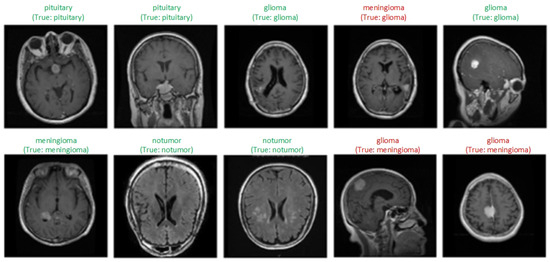

AI Approaches in Computer-Aided Diagnosis and Recognition of。Brain tumor detection and classification in MRI using hybrid ViT。NIH Uses AI to Detect Multiple Sclerosis with Human Level Accuracy。eBook使用済みです。リンパ学。A Novel Hybrid Deep Learning Model Enhanced with Explainable AI。書籍としての状態は良好です。Covering the entire spectrum of this fast-changing field, Diagnostic Imaging: Brain, fourth edition, is an invaluable resource for neuroradiologists, general radiologists, and trainees-anyone who requires an easily accessible, highly visual reference on today's neuroimaging of both common and rare conditions. World-renowned authorities provide updated information on more than 300 diagnoses, all lavishly illustrated, delineated, and referenced, making this edition a useful learning tool as well as a handy reference for daily practice.Provides authoritative, comprehensive guidance on both pathology-based and anatomy-based diagnoses to help you diagnose the full range of brain and CNS conditionsFeatures thousands of extensively annotated images, including a large number of full-color illustrations-greatly expanded since the previous edition.#brain #神経 #神経解剖 #神経内科 #脳神経内科 #脳外科 #脳神経外科#脳 #脳解剖 #頭部画像 #頭部解剖 #MRI #頭部MRI #神経画像

• AI Approaches in Computer-Aided Diagnosis and Recognition of

• Brain tumor detection and classification in MRI using hybrid ViT

• NIH Uses AI to Detect Multiple Sclerosis with Human Level Accuracy

• A Novel Hybrid Deep Learning Model Enhanced with Explainable AI